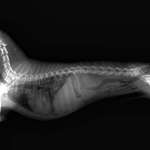

Unser Balou hat gestern im Laufe des Tages am ganzen Körper weiche Beulen gebildet. Als wir zum Tierarzt sind, meinte der "ich bin mir zu 90% sicher, dass das eine Wiener-Würstchen-Allergie, also eine Allergie gegen Schweinefleisch ist". Balou hat aber noch nie Schweinefleisch und schon gar keine Wü ...